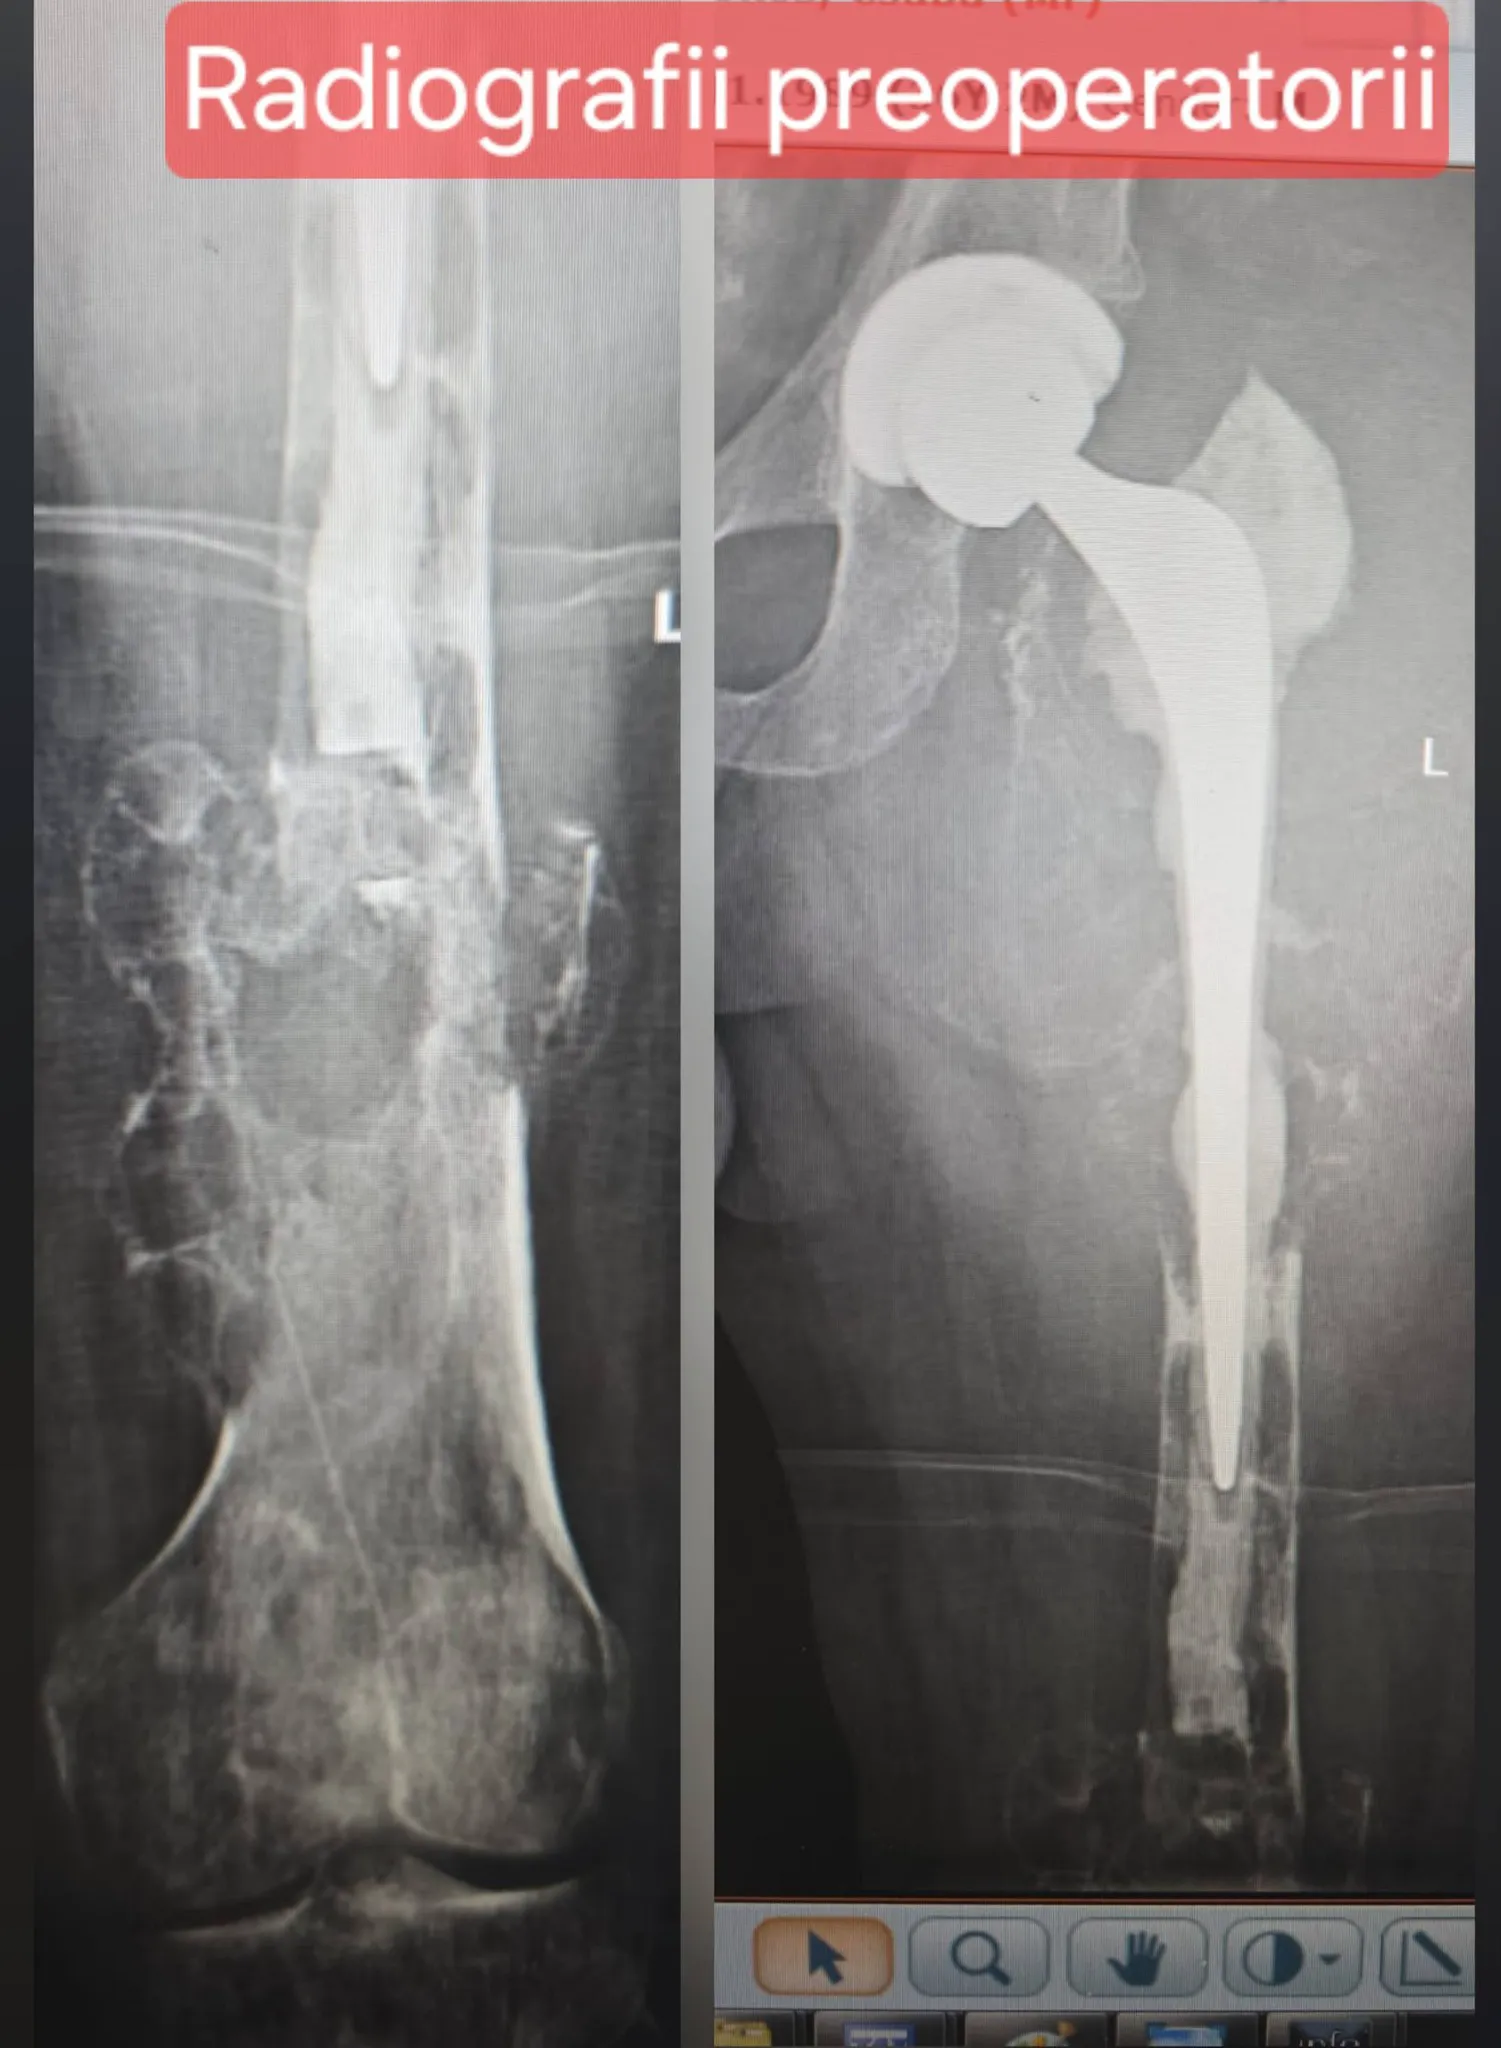

Pacientul, diagnosticat în urmă cu aproximativ trei ani cu displazie fibroasă femurală și ulterior cu chist osos anevrismal, suferise deja o fractură pe os patologic și o artroplastie de șold în străinătate, urmată de complicații și dureri persistente. Din cauza deteriorării extinse a femurului și a riscului ridicat de hemoragie, medicii au efectuat înaintea operației o embolizare vasculară, pentru a reduce sângerarea și a crește șansele de reușită.

Cazul este al unui pacient tânăr, în vârstă de 36 de ani, diagnosticat cu displazie fibroasă femurală în urmă cu aproximativ 3 ani, care la scurt timp după diagnostic a suferit o fractură pe os patologic de femur proximal, pentru care s-a intervenit într-un spital regional din Spania și s-a practicat artroplastia totală a șoldului cu o proteză primară. La mai puțin de 1 an post operator pacientul a prezentat din nou dureri cu decimentarea aseptică a implantului. Pacientul a fost internat ulterior în cadrul unui spital județean, unde s-a realizat o biopsie incizională cu stabilirea diagnosticului de chist osos anevrismal. Având în vedere complexitatea cazului, pacientul a fost transferat în secția de ortopedie a Spitalului Universitar de Urgență București.

Preoperator, având în vedere riscul hemoragic crescut, s-a practicat embolizarea principalelor surse vasculare, cu ajutorul medicilor din compartimentul de radiologie intervențională sub coordonarea dr. Bogdan Dorobăț”, se arată în anunțul făcut pe pagina de Facebook a SUUB.

„Intervenția, extrem de complexă, a presupus îndepărtarea integrală a femurului sever afectat de patologia tumorală și reconstrucția membrului inferior prin implantarea unei megaproteze tumorale personalizate. Operația a fost efectuată de o echipă multidisciplinară formată din medici ortopezi, medici anesteziști și personal medical auxiliar, într-un efort coordonat de către Prof. Univ. Dr. Catalin Cîrstoiu.

Această procedură reprezintă una dintre cele mai dificile intervenții din sfera ortopediei oncologice, fiind indicată în cazurile în care tumora afectează extensiv femurul și structurile adiacente și vine în sprijinul pacienților ca alternativă a tratamentelor radicale, precum amputația. Prin utilizarea megaprotezei tumorale, pacientului i se oferă șansa păstrării membrului și a unei recuperări funcționale semnificative.